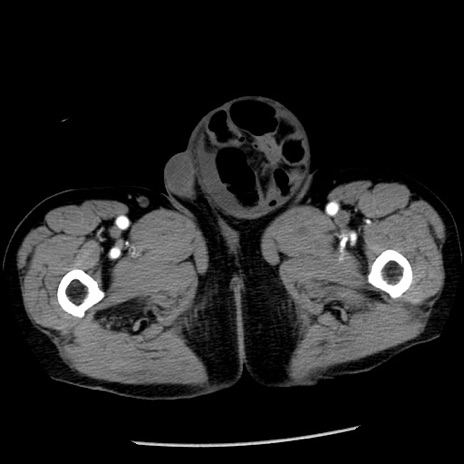

冠状断像